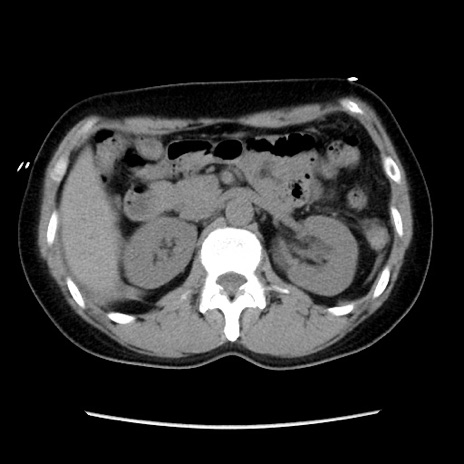

矢状断像

【症例】 50歳代女性

【主訴】 腹痛

【現病歴】前日生レバーを食べた。今朝に排便あり。 昼前に突然発症の腹痛を生じ、当院救急外来を受診した。

【既往歴】 子宮筋腫にてで子宮全摘後

【身体所見】 意識清明、腹部:平坦、軟、下腹部やや左を中心に圧痛・反跳痛あり、筋性防御あり

【データ】WBC 7800、CRP 0.07